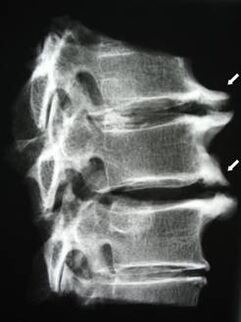

În stadiile inițiale, osteocondroza este detectată prin RMN. Ulterior, patologia poate fi diagnosticată folosind radiografie. La radiografiile coloanei cervicale, se observă o reducere a distanței dintre vertebre, modificări patologice ale articulațiilor fațetelor și osteofitoza.

Mulți oameni se plâng că nu își pot întoarce gâtul din cauza durerii severe atunci când ridică brusc ceva greu. Acest fenomen indică dezvoltarea unei hernie de disc. Cauza durerii în spate, gât și membrele superioare este ciupirea uneia dintre rădăcinile nervoase care iese din măduva spinării.